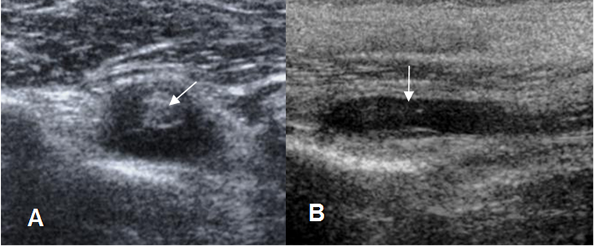

Fig 150. Tenosinovitis de la cabeza larga del bíceps.

A: Ecografía coronal. Cabeza larga del biceps completamente rodeada por líquido, secundario a tenosinovitis.

B: Ecografía sagital. Presencia de líquido en la corredera bicipital, por tenosinovitis.